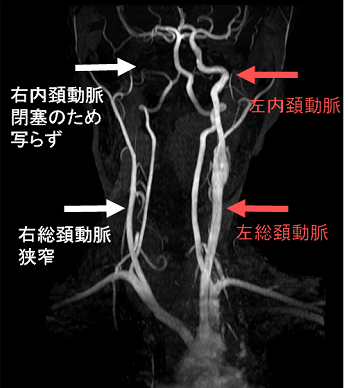

内頚動脈閉塞・狭窄、総頚動脈狭窄

甲状腺機能亢進症/バセドウ病で、内頚動脈閉塞・狭窄、総頚動脈狭窄を来す事があります。

下記の類もやもや病の異常血管網が発達する前の初期段階であろうと筆者は考えています。

写真は、長崎甲状腺クリニック(大阪)の自験例で、内頚動脈閉塞・狭窄、総頚動脈狭窄を認めます。

他の報告では、一過性脳虚血発作(TIA)を起こしています(BMC Neurol. 2019 Mar 2;19(1):34.)が、長崎甲状腺クリニック(大阪)の自験例では、脳神経症状は皆無でした(こんな不思議なことがあるんですね)。